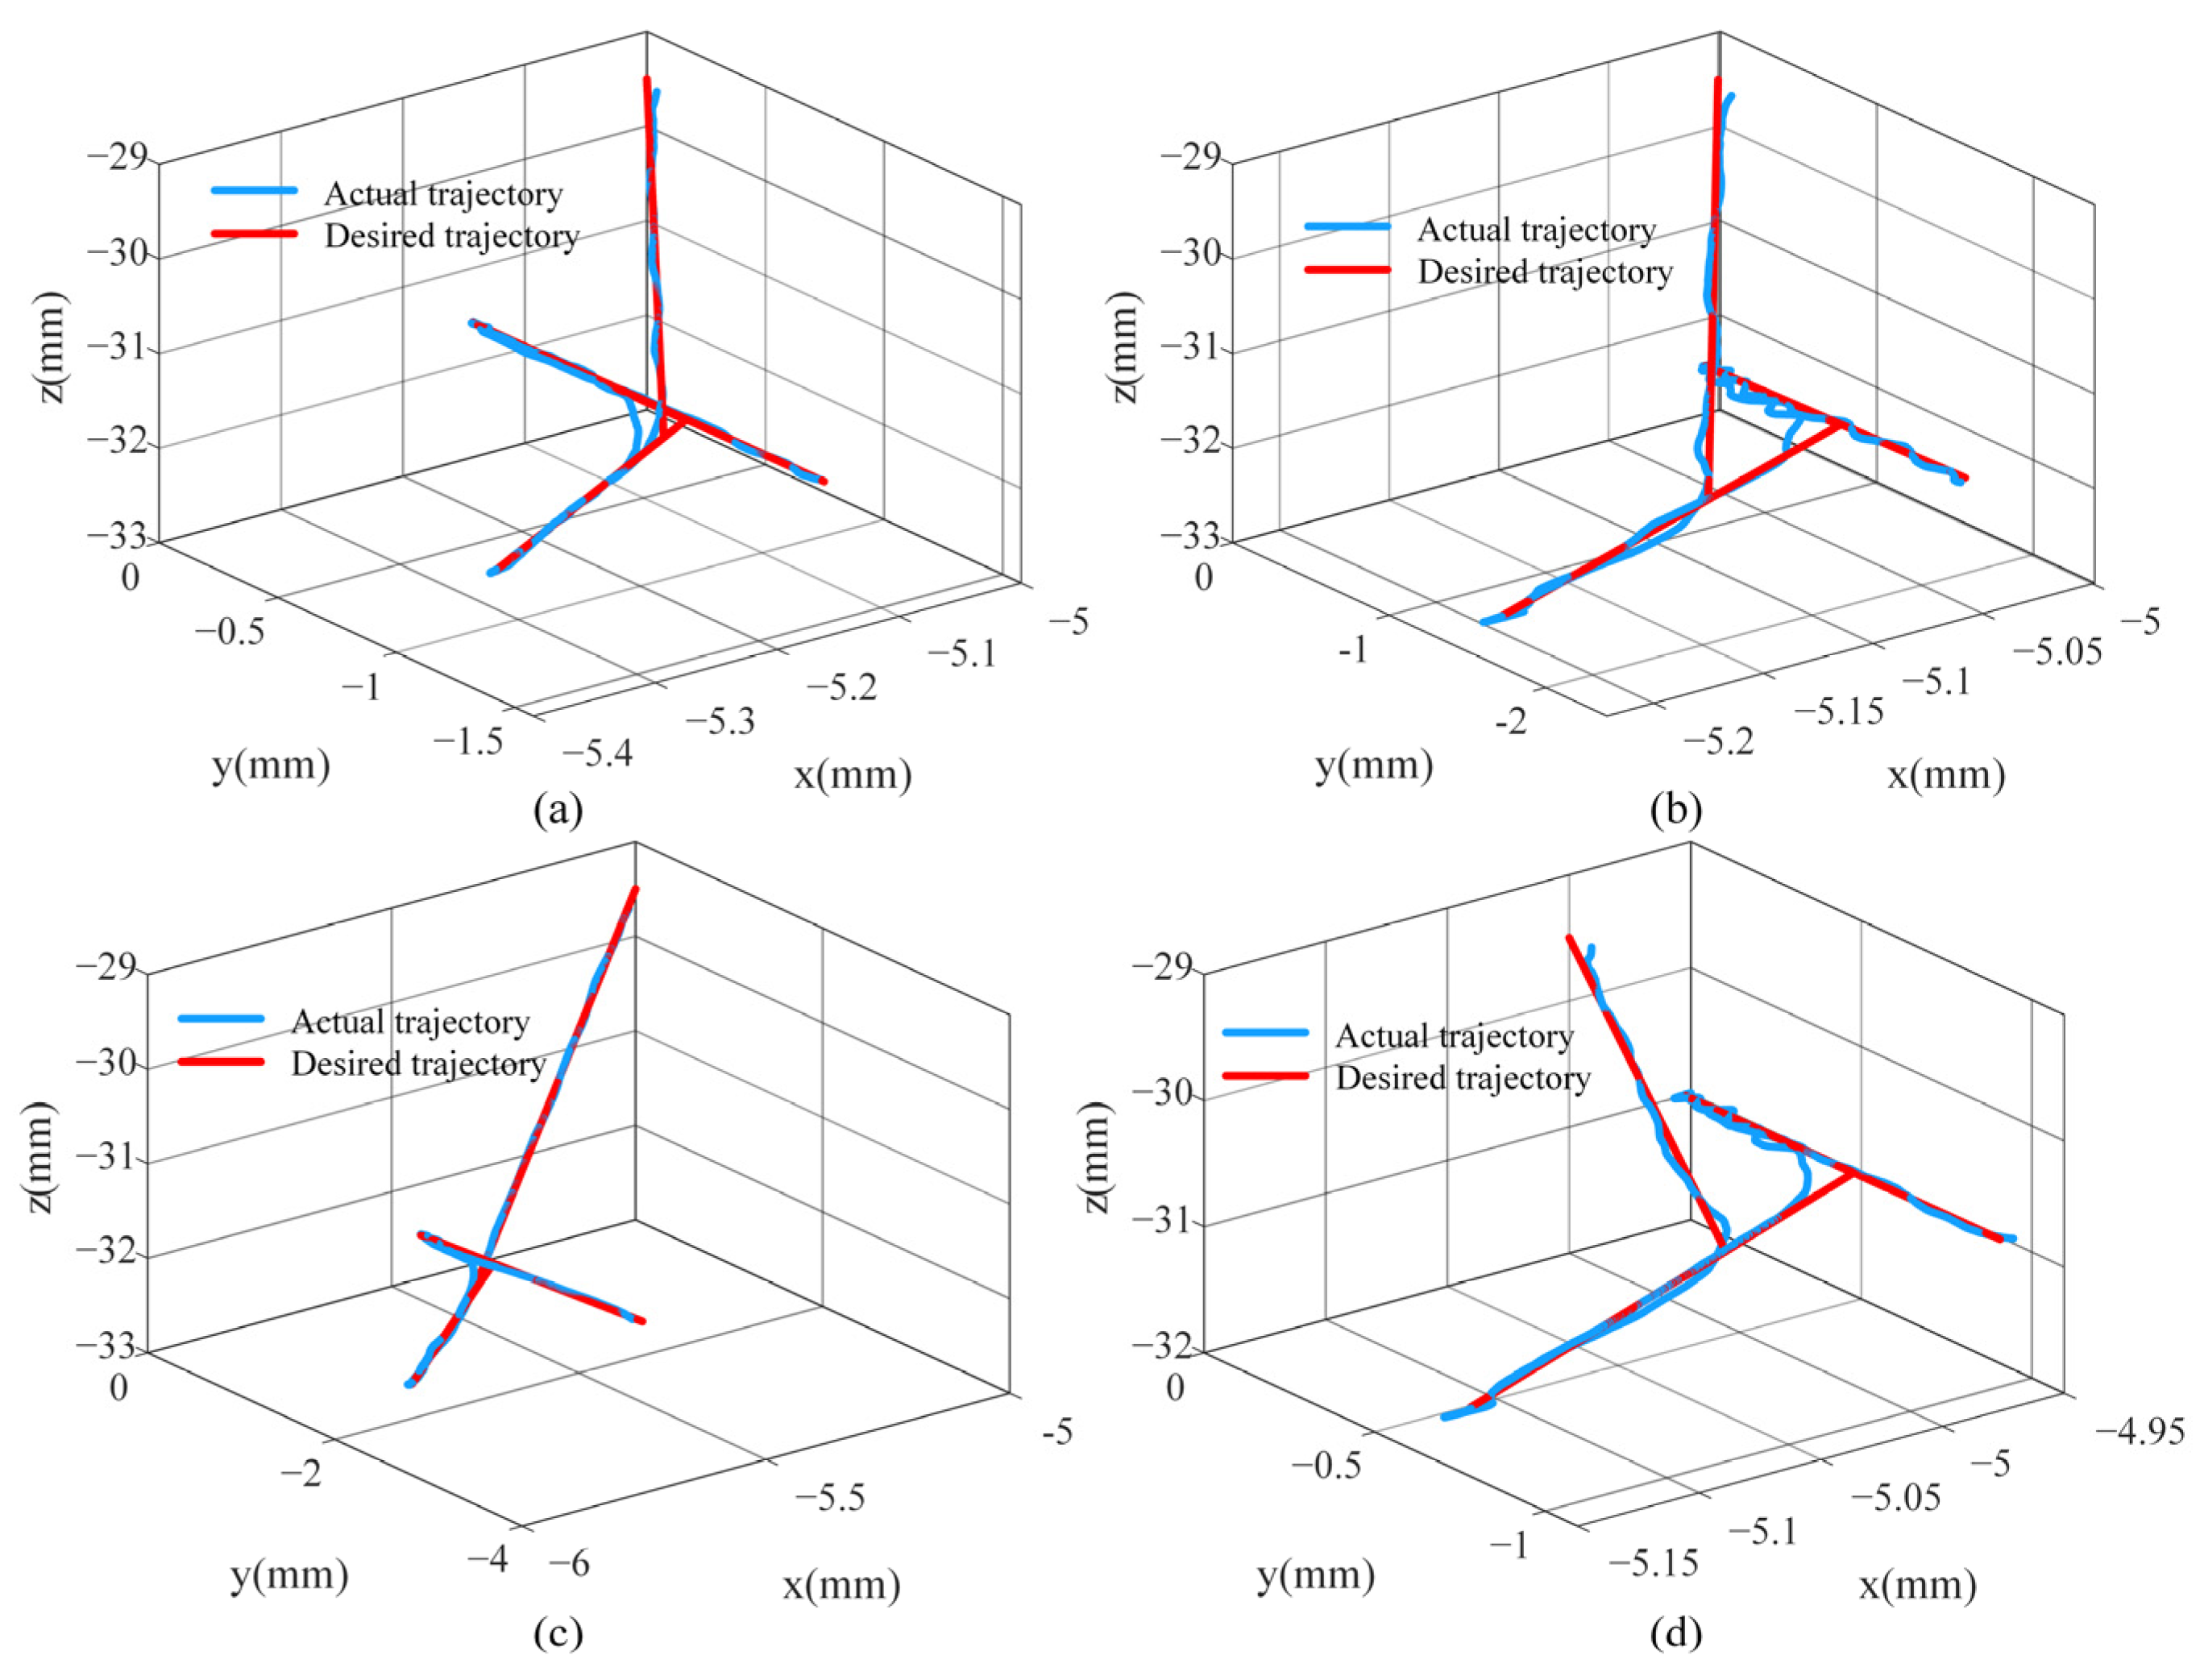

4.3. Break Initiation Experiment in ILM Peeling

| Error | Eye Phantom 1 | Eye Phantom 2 | Eye Phantom 3 | Eye Phantom 4 |

|---|---|---|---|---|

| x/μm | 18.275 | 21.345 | 18.332 | 17.532 |

| y/μm | 9.880 | 10.626 | 10.547 | 8.876 |

| z/μm | 21.920 | 23.598 | 19.249 | 21.823 |

| total/μm | 35.115 | 37.588 | 32.962 | 33.762 |